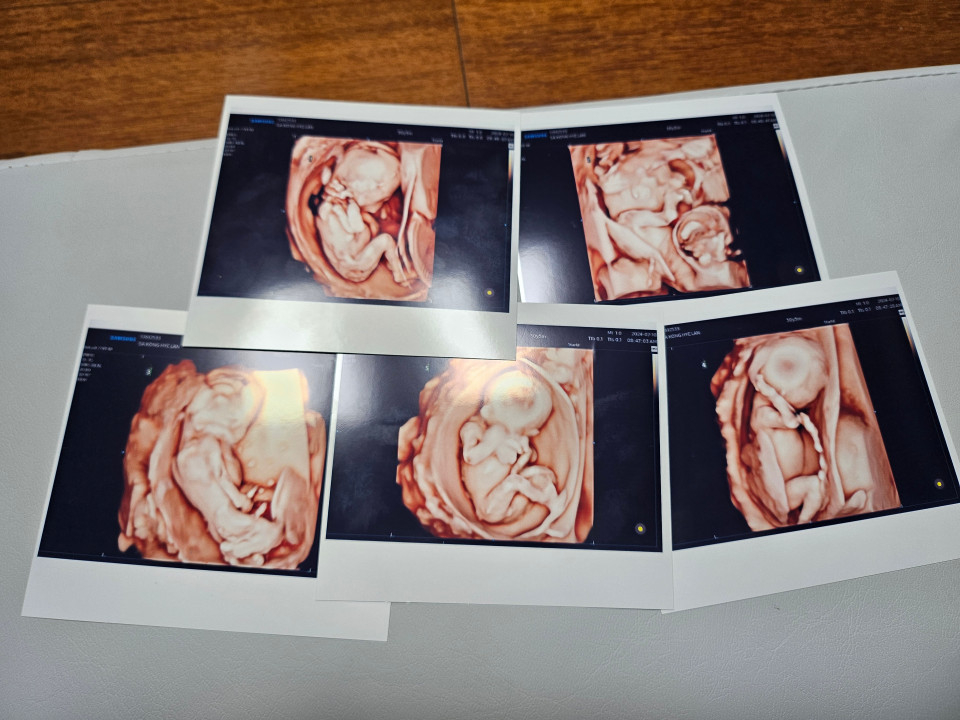

몇 년 전 국내에서 34년 만에 다섯 쌍둥이가 태어나 화제가 된 가운데, 서울성모병원에서 또 하나의 오둥이가 탄생했다. 다섯 쌍둥이는 세계적으로도 드문 사례다.

가톨릭대 서울성모병원 산부인과 홍수빈·소아청소년과 윤영아·신정민 교수팀은 20일 30대 산모의 다섯 신생아 다태아 분만을 성공리에 마쳤다고 이날 밝혔다. 자연임신으로 생긴 다섯쌍둥이를 분만한 국내 첫 사례다.

하지만 쌍둥이로 확인됐다. 그것도 둘이나 세쌍둥이가 아닌 다섯 쌍둥이라는 얘기에 첫 손주를 기다렸던 양가 어른들도 오둥이라는 소식에 걱정이 앞섰지만, 다섯 생명 모두를 지키기로 결심했다. 태명도 다섯으로 구성된 파워레인저에 빗대어 '팡팡레이저'가 됐다.